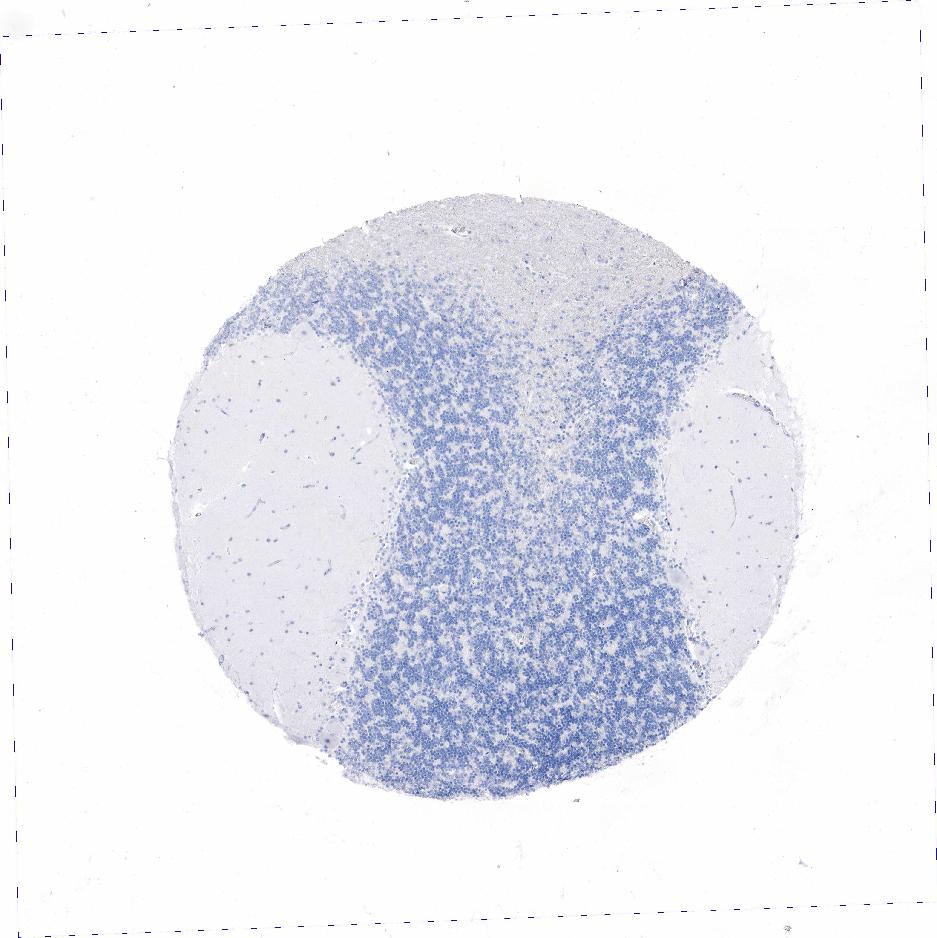

CEREBELLUM - Antibody stainingi

Antibody staining in the annotated cell types in the current human tissue is reported as not detected, low, medium, or high, based on conventional immunohistochemistry profiling in selected tissues. This score is based on the combination of the staining intensity and fraction of stained cells.

Each image is clickable and will lead to virtual microscopy that enables deeper exploration of all samples and also displays staining intensity scores, fraction scores and subcellular localization as well as patient and tissue information for each sample.

Antibody HPA017369Antibody CAB000023Antibody CAB040544Antibody CAB055506Antibody CAB058688

GLUC cells - cytoplasm/membrane -High---

Processes in granular layer -Medium---

Processes in white matter -Medium---